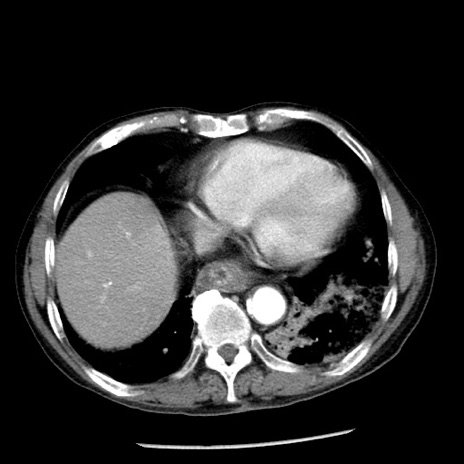

症例26(横断像)

【症例】80歳代男性

【主訴】嘔吐

【現病歴】昨晩2回嘔吐あり、今朝になっても嘔吐あり。来院。

【既往歴】胃潰瘍

【身体所見】意識清明、BT 37.6℃、BP 166/95mmHg、HR 100bpm、SpO2 97%、腹部:平坦・軟、腸蠕動音聴取良好、圧痛なし。

【データ】WBC 21900、CRP 1.46